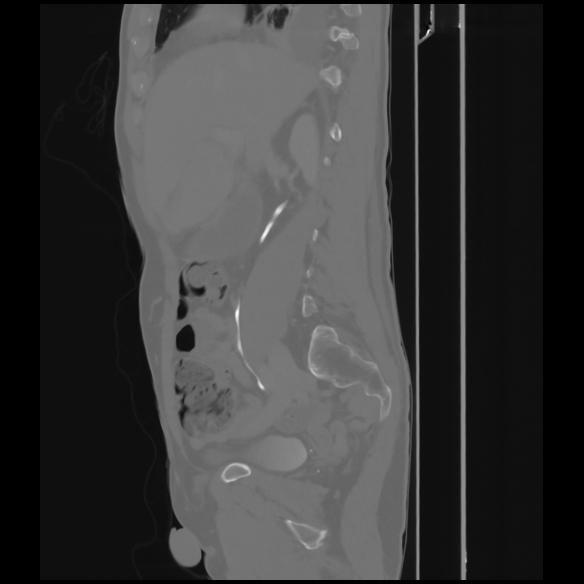

7 CUERPO,CE,Sagittal,3.000,CUERPO,Sagittal,